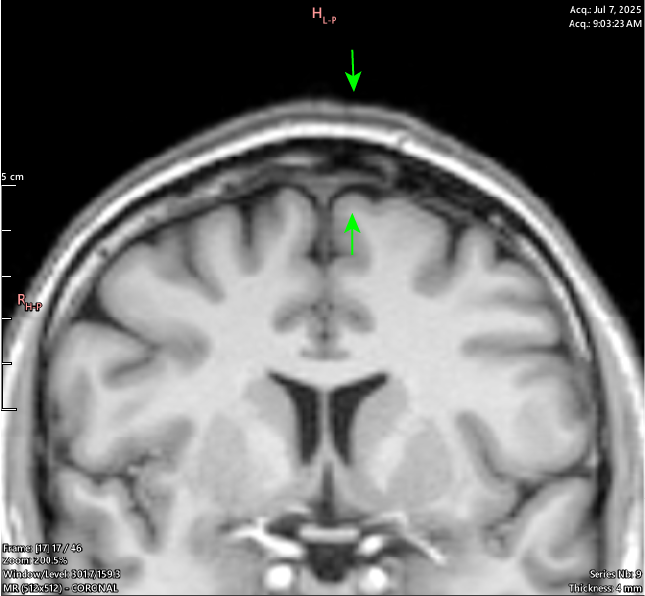

T1 Coronal

Coronal view shows this is happening along the Sagittal Suture - cranial sutures should return a uniform signal void (black) across all sequences as they are dense structures with little to no free water movement.

It can be seen throughout the JULY 2025 MRI series that a majority of the cranial sutures are instead filled with variable hypointense signaling describing dense, fibrous tissue.

By the age of 33 the cranial sutures should be almost - if not entirely - fused, showing as a thin (approx. 2mm) black zig-zag along their respective paths, if showing at all.

My Sagittal Suture in these images shows as 12.4mm wide at the outside margin, clearly showing atypical imaging presentation, indicating an underlying process occurring.

These are corresponding slices from 2 MRI series performed in OCT 2024 (left) and JULY 2025 (right). They show progressive, pathological boney change and osteolysis (bone destruction) over the 9 months between imaging. The yellow (OCT) and green (JULY) lines highlight visible and active bone destruction.

The pink is a significant region of interest as it shows not only the destruction of bone, but a “caving-in” change in the bone shape; Interestingly, this change is physically visible on the scalp as depicted below.